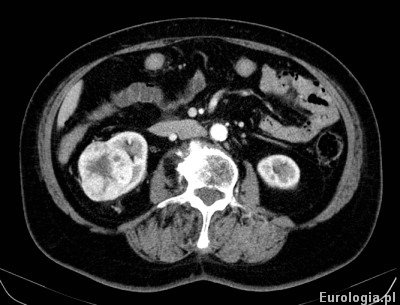

W razie konieczności podania kontrastu dożylnie konieczne jest założenie wenflonu. Tomografia z podaniem kontrastu - tak zwana tomografia dwufazowa pozwala na lepsze uwidocznienie zmian dobrze unaczynionych co jest szczególnie przydatne w diagnostyce guzów nerek.

Fot. Tomografia komputerowa przedstawiająca uwidaczniająca guza nerki prawej